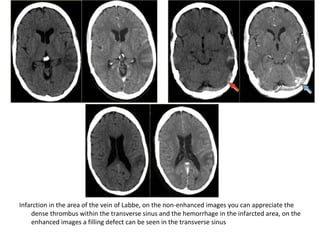

(a) FLAIR shows the venous infarction in the temporal lobe , (b) CT nicely

demonstrates the dense thrombosed transverse sinus (yellow arrow)